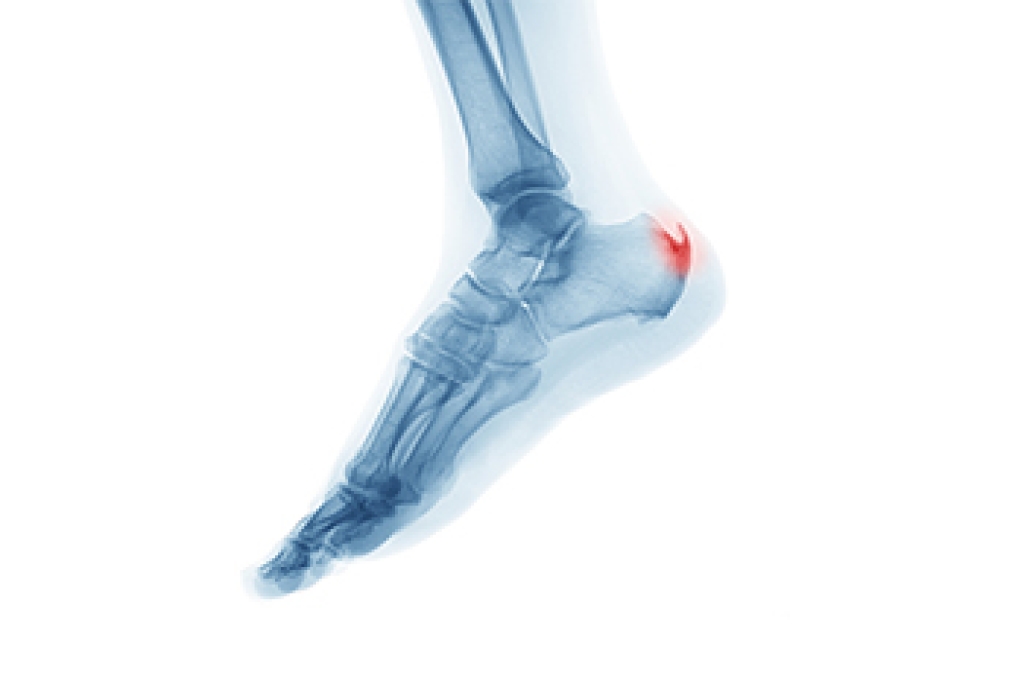

A heel spur is a bony growth that develops on the underside of the heel bone, often where the plantar fascia attaches. It typically forms over time as a response to ongoing stress or pressure on the foot. One of the main contributing factors is aging, as the tissues naturally lose elasticity and strength. Abnormal stress from repetitive activities, poor foot function, or walking patterns can place excessive strain on the heel. Carrying extra weight increases the load on the feet, which can lead to small tears in the plantar fascia. These micro-tears trigger inflammation and can encourage calcium deposits to build up, forming a spur. If you have heel pain, it is suggested that you schedule an appointment with a podiatrist who can accurately diagnose and treat heel spurs.

Heel spurs can be incredibly painful and sometimes may make you unable to participate in physical activities. To get medical care for your heel spurs, contact Cary Golub, DPM from New York. Our doctor will do everything possible to treat your condition.

Heels Spurs

Heel spurs are formed by calcium deposits on the back of the foot where the heel is. This can also be caused by small fragments of bone breaking off one section of the foot, attaching onto the back of the foot. Heel spurs can also be bone growth on the back of the foot and may grow in the direction of the arch of the foot.

Older individuals usually suffer from heel spurs and pain sometimes intensifies with age. One of the main condition's spurs are related to is plantar fasciitis.

Pain

The pain associated with spurs is often because of weight placed on the feet. When someone is walking, their entire weight is concentrated on the feet. Bone spurs then have the tendency to affect other bones and tissues around the foot. As the pain continues, the feet will become tender and sensitive over time.

Treatments

There are many ways to treat heel spurs. If one is suffering from heel spurs in conjunction with pain, there are several methods for healing. Medication, surgery, and herbal care are some options.